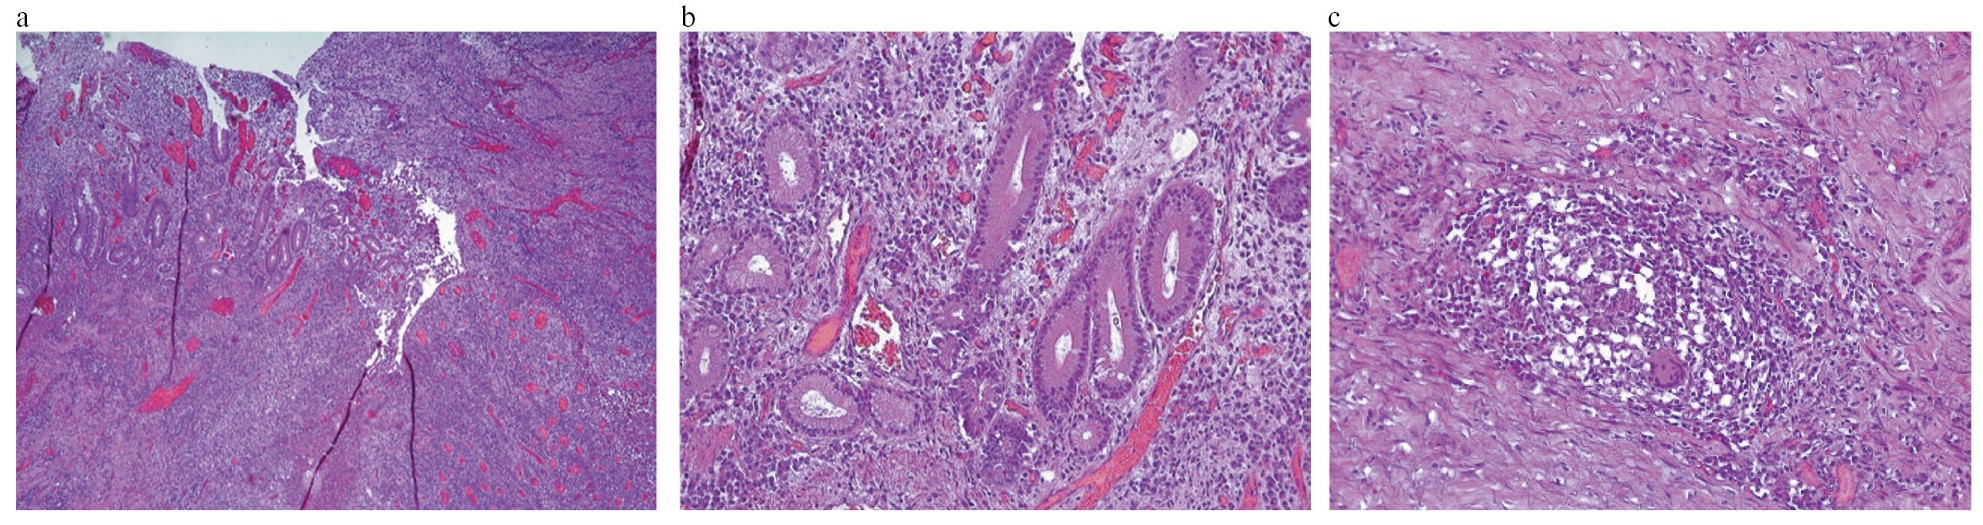

Осуществлен пересмотр стеклопрепаратов операционного материала от 2020 г. Заключение: гистологическая картина хронического очагового трансмурального воспаления толстой и подвздошной кишки с формированием глубоких эрозий, с участками гранулематозного воспаления, соответствующего БК в форме эрозивно-язвенного илеоколита (рис. 6).

Рис. 6. Хронический терминальный илеит БК: a – деструкция кишечных ворсин и крипт с формированием щелевидной язвы в слизистой оболочке подвздошной кишки; b – участки пилорической метаплазии в краях язвенного дефекта; c – эпителиоидноклеточная гранулема с гигантскими многоядерными клетками в толще мышечного слоя. Окраска гематоксилином и эозином. Увеличение: a – ×90; b, c – ×300.

Fig. 6. Chronic terminal ileitis of Crohn's disease: a – destruction of intestinal villi and crypts with the formation of a slit ulcer in the mucous membrane of the ileum; b – areas of pyloric metaplasia at the edges of the ulcerative defect; c – epithelioid cell granuloma with giant multinucleated cells in the thickness of the muscle layer. Stained with hematoxylin and eosin. Magnification: a – ×90; b, c – ×300.

Обращали на себя внимание присутствие в подслизистом слое большого количества эпителиоидно-клеточных гранулем с гигантскими многоядерными клетками без признаков казеозного некроза, наличие множества гигантских многоядерных клеток в лимфатических фолликулах слизистой оболочки, лимфатических узлах, а также свободно лежащих среди волокнистых структур подслизистого слоя. Данные изменения наблюдаются при генерализованной туберкулезной инфекции и не характерны для БК (рис. 7, 8).

Рис. 7. Специфическое гранулематозное воспаление при ТБ толстой кишки: a – гиперплазия лимфоидной ткани с множественными эпителиоидноклеточными гранулемами; b – эпителиоидноклеточные гранулемы с участками казеозного некроза. Окраска гематоксилином и эозином. Увеличение: a – ×90, b – ×300.

Fig. 7. Specific granulomatous inflammation in tuberculosis of the colon: a – hyperplasia of lymphoid tissue with multiple epithelioid cell granulomas; b – epithelioid cell granulomas with areas of caseous necrosis. Stained with hematoxylin and eosin. Magnification: a – ×90, b – ×300.

Рис. 8. Трансмуральное гранулематозное воспаление в стенке толстой кишки при генерализованном ТБ: a – множественные эпителиоидноклеточные гранулемы в слизистой оболочке и подслизистом слое; b – липоматоз и фиброз подслизистого слоя; c – многоядерные клетки, свободно лежащие среди волокнистых структур. Окраска гематоксилином и эозином. Увеличение: a, b – ×90; c – ×300.

Fig. 8. Transmural granulomatous inflammation in the colon wall in generalized tuberculosis: a – multiple epithelioid cell granulomas in the mucous membrane and submucosal layer; b – lipomatosis and fibrosis of the submucosal layer; c – giant multinucleated cells lying freely among fibrous structures. Stained with hematoxylin and eosin. Magnification: a, b – ×90; c – ×300.